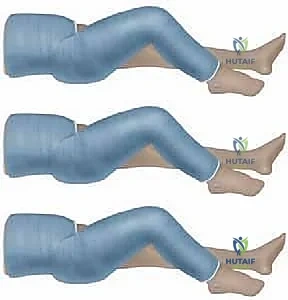

The procedure typically begins with the application of a long-leg cylinder cast on the injured extremity. We utilize a hybrid casting technique: an inner layer of plaster of Paris for superior conformability and molding, followed by an outer layer of fiberglass for structural rigidity and weight reduction. For a traditional spica, the knee is flexed.

TECH FIG 1 • A. Cylinder cast with 90 degrees of knee flexion for traditional spica casting.

While 90 degrees of knee flexion (as seen in TECH FIG 1A) has been the historical standard to control rotation and prevent the child from slipping out of the cast, modern literature has heavily scrutinized this practice due to the elevated risk of compartment syndrome. Many contemporary surgeons now advocate for 60 to 70 degrees of knee flexion, and increasingly, leaving the foot and ankle free (a "walking spica" modification) if the fracture pattern is stable enough.